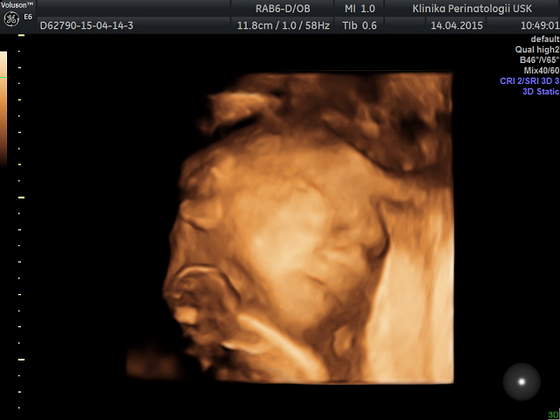

Ja też dziś miałam usg ale to młodzi doktorzy robili, więc bez szczegółów... mieli problem ze złapaniem czegokolwiek ale kawałek twarzyczki widać, szkoda tylko że nóżek nie chciał rozłożyć żeby pisiorka pokazać

a to Tymonek 24t 4d

O jaki dziubek slodki sobie śpi:-*

Dzięki dziewczyny :-* ja nie mogę się napatrzeć :-) jak zobaczyłam nosek to od razu powiedziałam że kinolek jak u tatusia